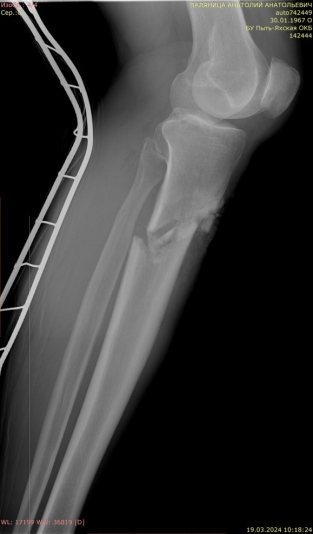

3) Мужчина, 52 года. Производственная травма в результате падения трубы с высоты двух метров на область голени. Открытый оскольчатый перелом большеберцовой и малоберцовой костей правой голени в средней трети со смещением отломков. Обширная рвано-ушибленная рана правой голени с дефектом мягких тканей (рис. 7).

Рис. 7.

В экстренном порядке выполнены ПХО раны, фиксация перелома аппаратом внешней фиксации, на рану наложены наводящие швы (рис. 8).

Рис. 8.

В послеоперационном периоде сформировался некроз в области послеоперационной раны. Были выполнены некрэктомия, пластика кожного дефекта методом свободной кожной пластики.

Через 27 дней после травмы был выполнен окончательный блокируемый остеосинтез правой большеберцовой кости интрамедуллярным стержнем с антибактериальным покрытием (рис. 9).

Рис. 9.